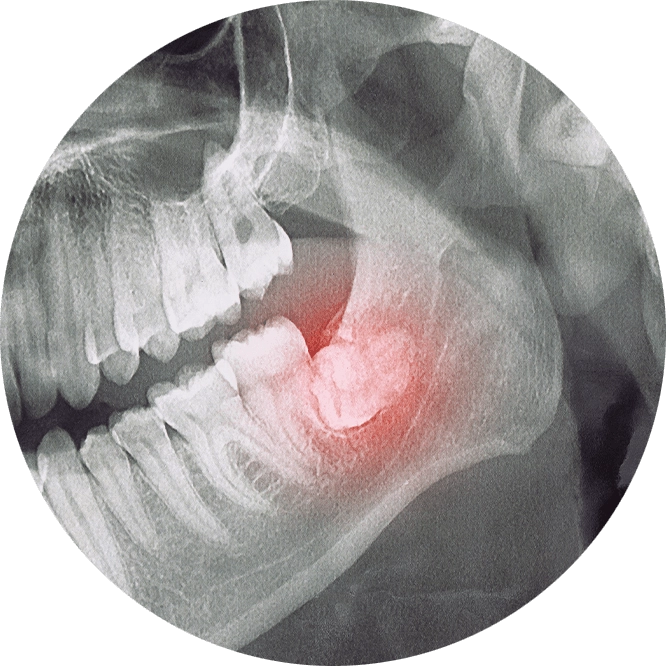

The decision to perform an extraction is typically straightforward when a tooth is affected by significant decay, severe periodontal disease, or a fracture. Digital X-rays are used to analyze the underlying structures and determine if the tooth can be saved. If there is a pulp infection without a tooth fracture, root canal therapy is a highly successful method for preventing extraction.

Extraction of normal teeth may be required for orthodontics, full mouth dental implants, or when a primary tooth hasn't fallen out and is preventing a permanent tooth from erupting. At Kari Mann Dental Studio in Cape Coral, our goal is always to save natural teeth. However, if conservative treatment is ineffective, extraction may be necessary. Removing a damaged or abscessed tooth can prevent more serious issues from impacting other teeth, your oral health, and even your physical health.

A blood clot typically forms over the empty tooth socket during healing. If the blood clot doesn't form or gets dislodged, this can expose the bone and nerves below the socket and lead to dry socket. While this painful complication only occurs in an estimated 0.5 to 5.6% of simple extractions, dry socket can affect up to 30% of cases following surgical removal of wisdom teeth. Dry socket isn't completely avoidable, but you can help prevent it and safeguard a smooth recovery by following our guidelines.